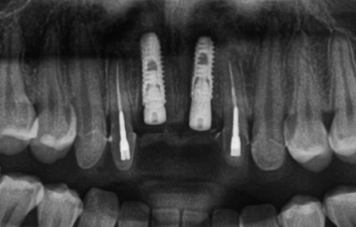

앞니는 구조적으로 뼈가 얇고 치아를 상실한 뒤 뼈 흡수가 빠르게 진행되어 까다롭습니다. 정확한 위치에 식립하지 않으면 심미적으로 만족도가 떨어질 수 있어 3D CT 기반 정밀 진단을 통해 정확도 높은 수술 계획을 수립합니다.